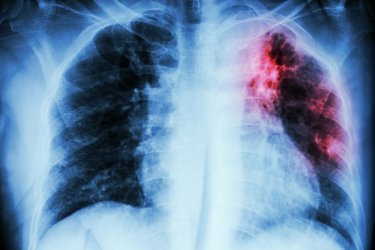

Akciğer kanseri dünyada kanser türleri arasında en sık görülen ve yine en sık ölüme neden olan kanser türü olarak ilk sırada yer alıyor. Öyle ki tüm kanser ölümlerinin yaklaşık 3’te birinden akciğer kanseri sorumlu oluyor. Dünyada her yıl yaklaşık 2,2 milyon kişi sigaranın en önemli risk faktörü olduğu akciğer kanserine yakalanıyor ve 1,6 milyon kişi de bu hastalık nedeniyle hayatını kaybediyor.

Yeni Akit/Ankara Ülkemizde de akciğer kanseri oldukça yaygın görülüyor. 2020 yılında 40 binin üzerinde yeni akciğer tanısı konulduğu belirtiliyor. Akciğer kanseri, genellikle erken dönemlerinde fazla belirti vermemesi veya en tipik belirtisi olan öksürük geliştiğinde sigara içen kişilerin ‘sigara öksürtüyor’ düşüncesiyle hekime geç başvurmaları nedeniyle sıklıkla ileri evrede teşhis ediliyor. Tedavinin gecikmesi de hastanın hayatını kaybetmesine yol açıyor. Acıbadem Ataşehir Hastanesi Göğüs Cerrahisi Uzmanı Prof. Dr. Erdal Okur, oysa gerek cerrahi tedavide gerekse diğer tedavi yöntemlerinde yaşanan önemli gelişmeler sayesinde özellikle erken tanı konabilen ve cerrahi olarak tedavi edilebilen akciğer kanserinden tamamen kurtulmanın mümkün olabileceğini belirterek, “Hastalığın erken döneminde tanı konabilmesi için yüksek riskli olarak belirlenmiş, yoğun sigara içen veya geçmişte içmiş olan 50 yaş üzeri kişilere her yıl düşük radyasyon dozlu bilgisayarlı akciğer tomografi çekimi yapılması öneriliyor. Bu sayede henüz hiçbir belirti vermemiş erken evre akciğer kanserinin yakalanması mümkün olabiliyor” diyor. Peki hangi belirtiler akciğer kanserine işaret ediyor, ne zaman hekime başvurmak gerekiyor? Göğüs Cerrahisi Uzmanı Prof. Dr. Erdal Okur, “1-30 Kasım Dünya Akciğer Kanseri Farkındalık Ayı” kapsamında akciğer kanserinin belirtilerini anlattı; önemli uyarılarda bulundu!